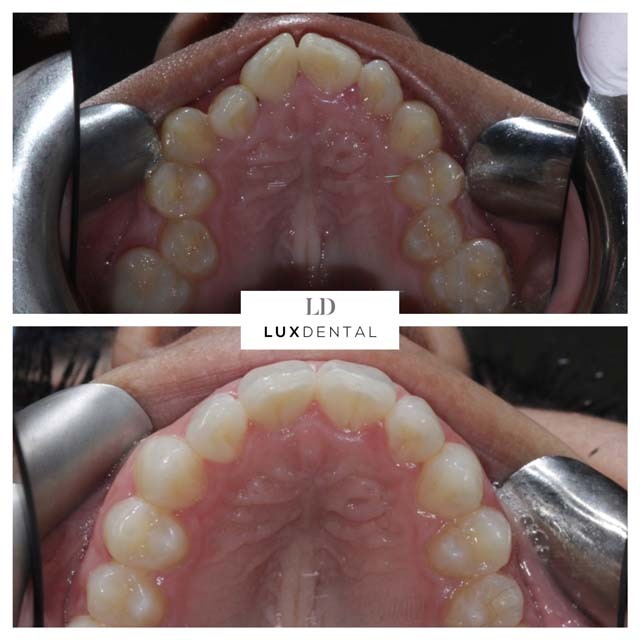

Smile Gallery